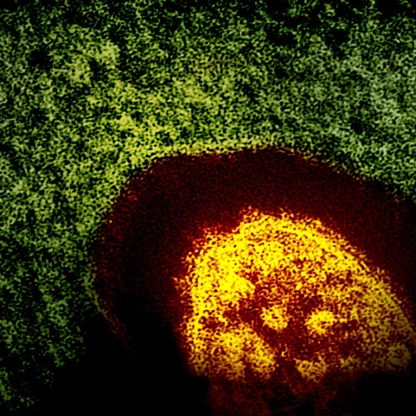

Measles is a highly contagious disease caused by a virus. It spreads through the air when an infected person coughs or sneezes. It can be very serious and cause hospitalizations, serious health complications and even death. The best way to prevent measles is to get vaccinated.